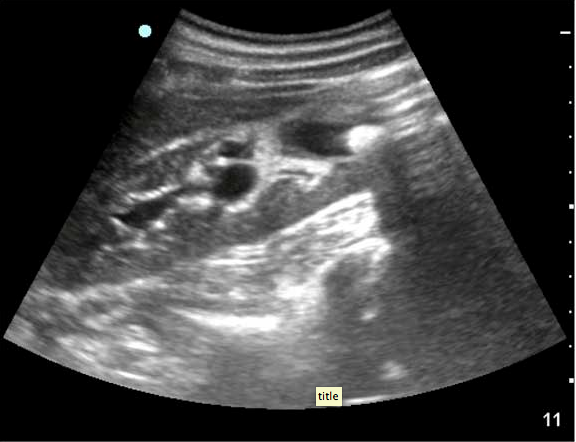

They describe it best: ” ….60-year-old male who collapsed at work and remained unresponsive. They state that there was bystander CPR and a lot of freaking out by coworkers. The only past history they have was from a coworker who thought he had high blood pressure. There was also a witness who told them he was just walking, then doubled over and collapsed without saying a thing. No one knew if he had any symptoms earlier in the day. Paramedics state he was initially in a PEA rhythm at a rate of 120 bpm on the monitor. They started an IV, gave him a 500cc saline bolus, intubated him, and have given three rounds of epi. They estimate a 15 minute down time prior to their arrival and a 10 minute transport time with no return of spontaneous circulation. In fact, things are going in the opposite direction as he has been in asystole for the past five minutes.

They move him onto the bed where your EMT takes over CPR. You note good and symmetric assisted breath sounds via the ET tube, but minimal palpable femoral pulse despite what appears to be good CPR to the tempo of the Bee Gees hit “Staying Alive”. On the monitor there is asystole in two leads. Pupils are fixed and dilated despite no atropine having been received. Things are not looking promising.

You request saline wide open and a final round of epinephrine while you take a look for cardiac motion with the ultrasound machine. To minimize interruption of CPR you don’t have the EMT pause until you are completely ready to look. You also have the RT hold respirations to avoid any artifact. There is no cardiac motion. You verbalize this to your team. The heart does not appear dilated and there is no pericardial effusion. You ask aloud, “anyone have any other suggestions” prior to calling the time of death.

Of course you next wonder what did him in: MI, PE, something else… His belly looks pretty protuberant, so you decide to take a quick look at his abdomen to check for free fluid. What you see is shown in the two images below. ”

Screen Shot 2013-08-27 at 6.26.16 PM

What do you think killed this gentleman? Trust me, you want to read more and see what exactly the ultrasound image is  – as it is quite an interesting finding: go here.